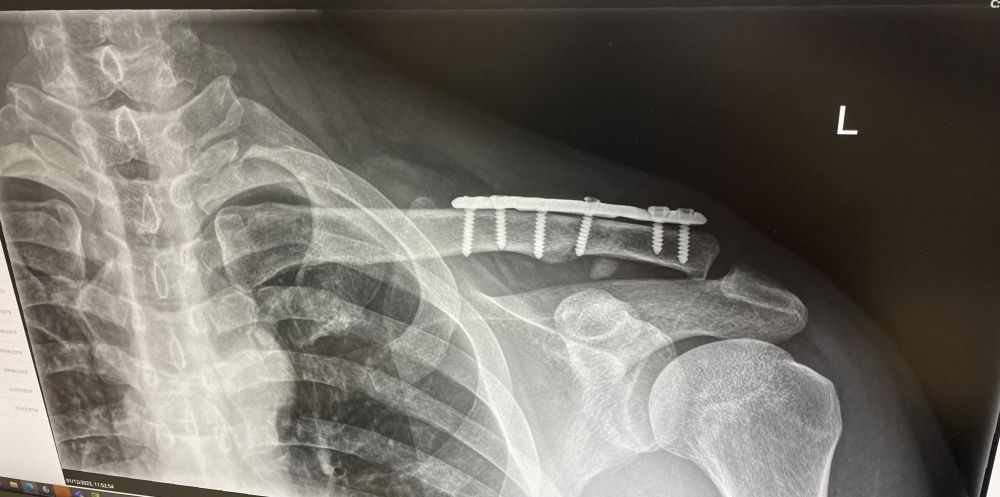

手术后用了六颗螺丝固定,医院说钛片可以一直保留在体内,抄刀医生跟我说:一年后回来我帮你取出,一个简单的小手术